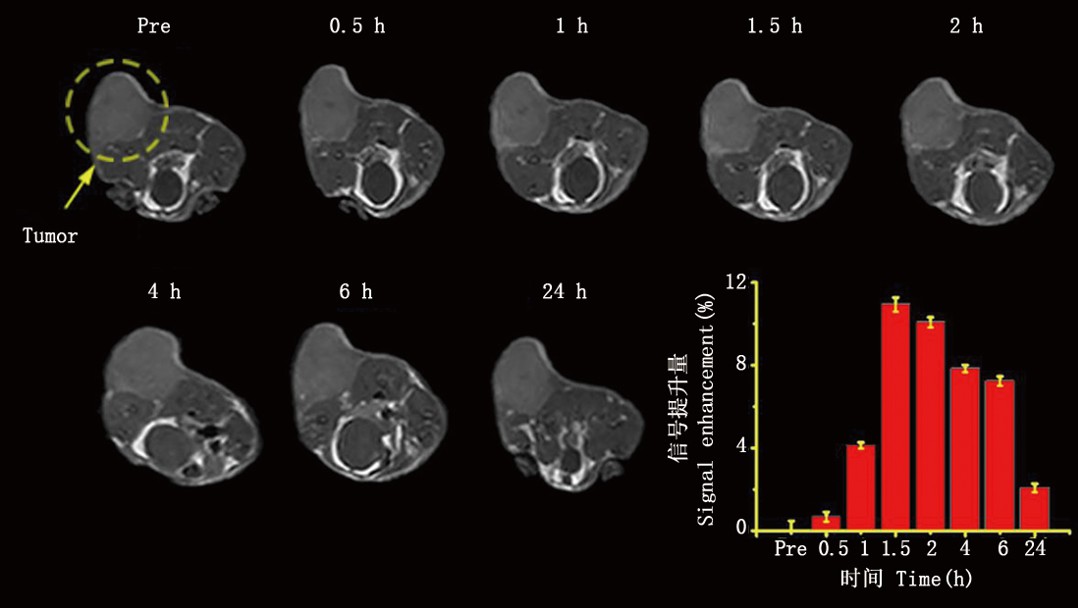

实验动物用核磁共振成像是在同种动物模型的情况下研究某些疾病的生物学和生理学特征的理想方法。实验动物用核磁共振成像还可以用于研究器官、肿瘤、血管和组织的结构和功能。

广泛应用:实验动物MRI成像广泛应用于心血管学、肿瘤学和组织工程学等域,提供了充足的信息和数据,有利于细致深入地研究生命科学问题。